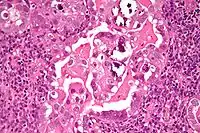

Histology H&E of uterine serous papillary carcinoma. H&E stain.

Histopathologically, uterine serous carcinomas is typically characterized by (1) nipple-shaped structures (papillae) with fibrovascular cores (2) marked nuclear atypia (irregularities in the nuclear membrane, enlarged nuclear size), (3) psammoma bodies and (4) cilia.